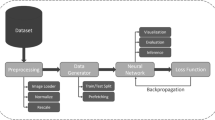

This paper presents an adaptive denoising approach aiming to improve the visibility and detectability of hemorrhage from brain computed tomography (CT) images. The suggested approach fuses the images denoised by total variation (TV) method, denoised by curvelet-based method, and edge information extracted from the noise residue of TV method. The edge information is extracted from the noise residue of TV method by processing it through curvelet transform. The visual interpretation shows that the proposed approach not only reduces the staircase effect caused by total variation method but also reduces visual distortion induced by curvelet transform in the homogeneous areas of the CT images. The denoising abilities of the proposed method are further evaluated by segmenting the hemorrhagic brain area using region-growing method. The sensitivity, specificity, Jaccard index, and Dice coefficients were calculated for different noise levels. The comparative results show that the significant improvement has yielded in the brain hemorrhage detection from CT images after denoising it with the proposed approach.